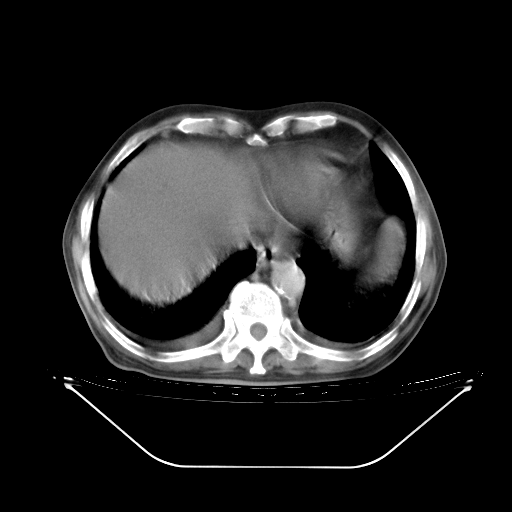

5月9日肺部CT(在4月27日齐鲁医院肺部CT描述部分肺组织磨玻璃样改变,12天后肺组织广泛磨玻璃样改变)

2009年5月9日肺部CT

大致读了系列胸部CT:纵隔窗无明显异常,肺窗:从4、27至今:主要是双肺中下野外带可见毛玻璃样改变,目前处于急性肺泡炎阶段,至于原因考虑1、结替组织或胶原血管性疾病所致?2、恶性疾病如恶组在肺部所致的表现或细支气管肺泡癌?3、药物或其它原因如肺蛋白沉着症所致肺泡炎目前不太可能?总之,明天就去请我院的呼吸科、感染科、血液科和临免专家会诊哈。